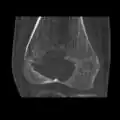

A variety of imaging studies can be used to diagnose chondroblastoma, with radiographs being the most common.[10][8] Laboratory studies are not considered useful.[14] Classical chondroblastoma (appearing on long bones) appears as a well-defined eccentric oval or round lytic lesion that usually involves the adjacent bone cortex without periosteal reaction.[10][13] A sclerotic margin can be seen in some cases.[10][13] For long bone chondroblastomas the tumor is typically contained to the epiphysis or apophysis but may extend through the epiphyseal plate.[10][13] Chondroblastomas are usually located in the medullary portion of bones and can, in some cases, include the metaphysis.[10][13] However, true metaphyseal chondroblastomas are rare and are typically the result of an extension from a neighboring epiphyseal legion.[10][13] Most lesions are less than 4 cm.[10] A mottled appearance on the radiograph is not atypical and indicates areas of calcification which is commonly associated with skeletally immature patients.[10] Additionally, one-third of all cases involve aneurysmal bone cysts which are thought to be the result of stress, trauma or hemorrhage.[10] In cases involving older patients or flat bones, typical radiographic presentation is not as common and may mimic aggressive processes.[10][13]

Other imaging techniques involve computed tomography (CT), magnetic resonance imaging (MRI), and bone scans, which may be helpful in determining the anatomical boundaries, associated edema, or biological activity of the chondroblastoma, respectively.[8][10] MRI studies may show extensive oedema around the lesion and show variable T2 signal intensity.[15]

1. a. X-ray of chondroblastoma of thigh bone near knee -

1. b. CT scan shows chondroblastoma of thigh bone near knee more clearly -